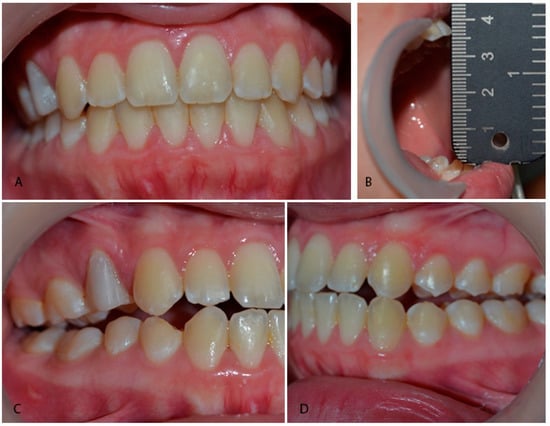

Figure 2.

Intraoral photos of the (A) dental occlusion; (B) maximum opening; and (C,D) mandibular lateral excursions, showing the stability of the mandibular dynamics ten years after the myofunctional treatment of the mandibular condylar fracture.